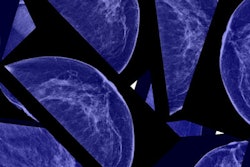

As the U.S. celebrates this year's Breast Cancer Awareness Month, radiology experts and advocates reflect on the big year that breast imaging has had.

From the U.S. Food and Drug Administration’s (FDA’s) mandate on breast density notification taking effect to state- and federal-level legislation being introduced and passed for insurance coverage on supplemental imaging, breast imaging is poised to experience transformation soon, the experts said.